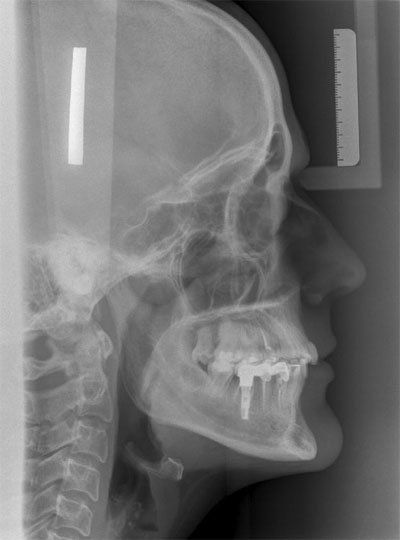

La cefalometría es una técnica diagnóstica de gran utilidad en el campo de la odontología en general y en los tratamientos de ortodoncia en particular. Permite obtener una imagen y medidas concretas del cráneo del paciente a partir de radiografías tomadas desde diferentes ángulos.

Se realiza una composición en tres dimensiones de la estructura ósea y se establecen los puntos anatómicos más significativos, como por ejemplo los huesos, las piezas dentales y los músculos faciales, entre otros.

Nuestro trabajo consiste en la realización de diferentes trazados de teleradiografías a través de una serie de imágenes que hemos recibido por parte de nuestro cliente vía telemática o en formato físico. En nuestro centro juntamos todas las imágenes y hacemos una composición en tres dimensiones que permite conocer las medidas exactas de la estructura ósea del paciente y el correspondiente diagnóstico.